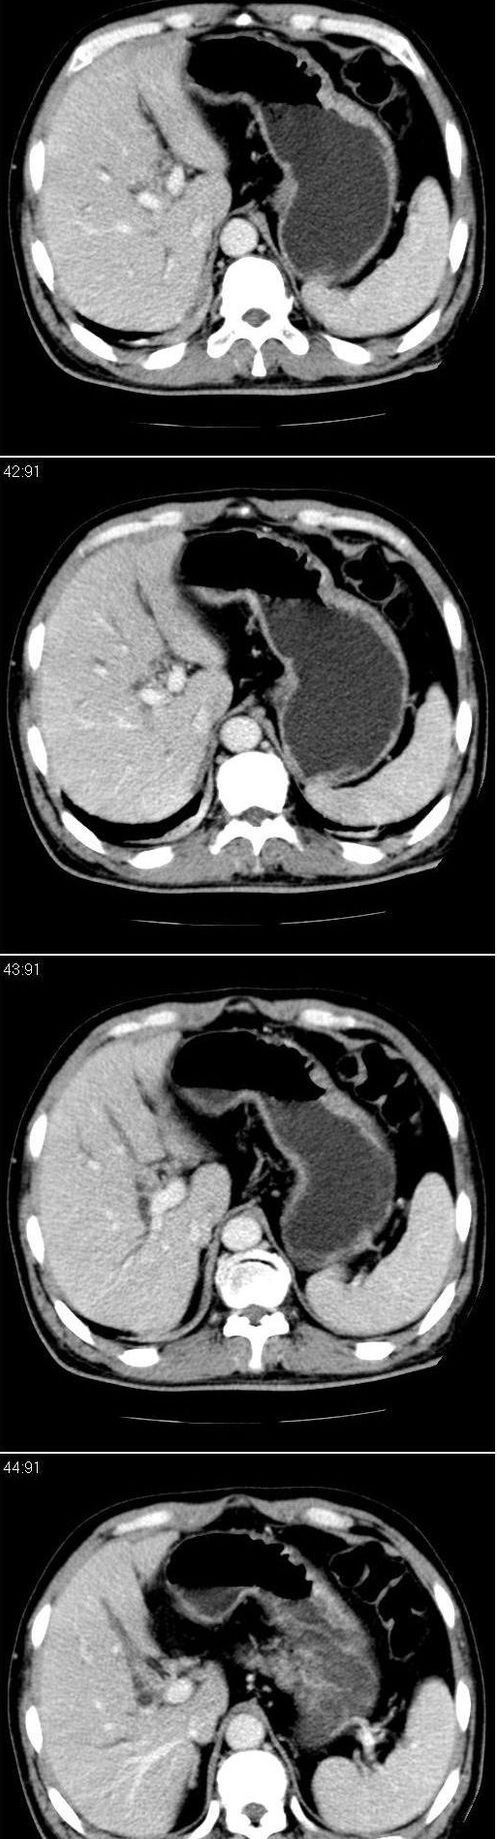

标题: CT13147:男,57岁。因胆结石阻塞性黄疸入院。 [打印本页]

标题: CT13147:男,57岁。因胆结石阻塞性黄疸入院。

男,57岁。因胆结石阻塞性黄疸入院。这是胆囊切除术后的照片,看看此片到底有什么问题。

肝内外胆管轻度扩张,胆囊窝内见引流管考虑胆囊切除术后改变.胃窦部软组织似增厚,建议胃镜检查.

在手术切除胆囊的过程中,发现肝门部胆总管恶性占位,因为家属不同意手术,没有切除,能看出来么?

肝内外胆管轻度扩张。楼主提示左右肝管合汇区域壁稍厚。胆总管末段壁似也稍厚有轻度强化。就现有资料诊断难。